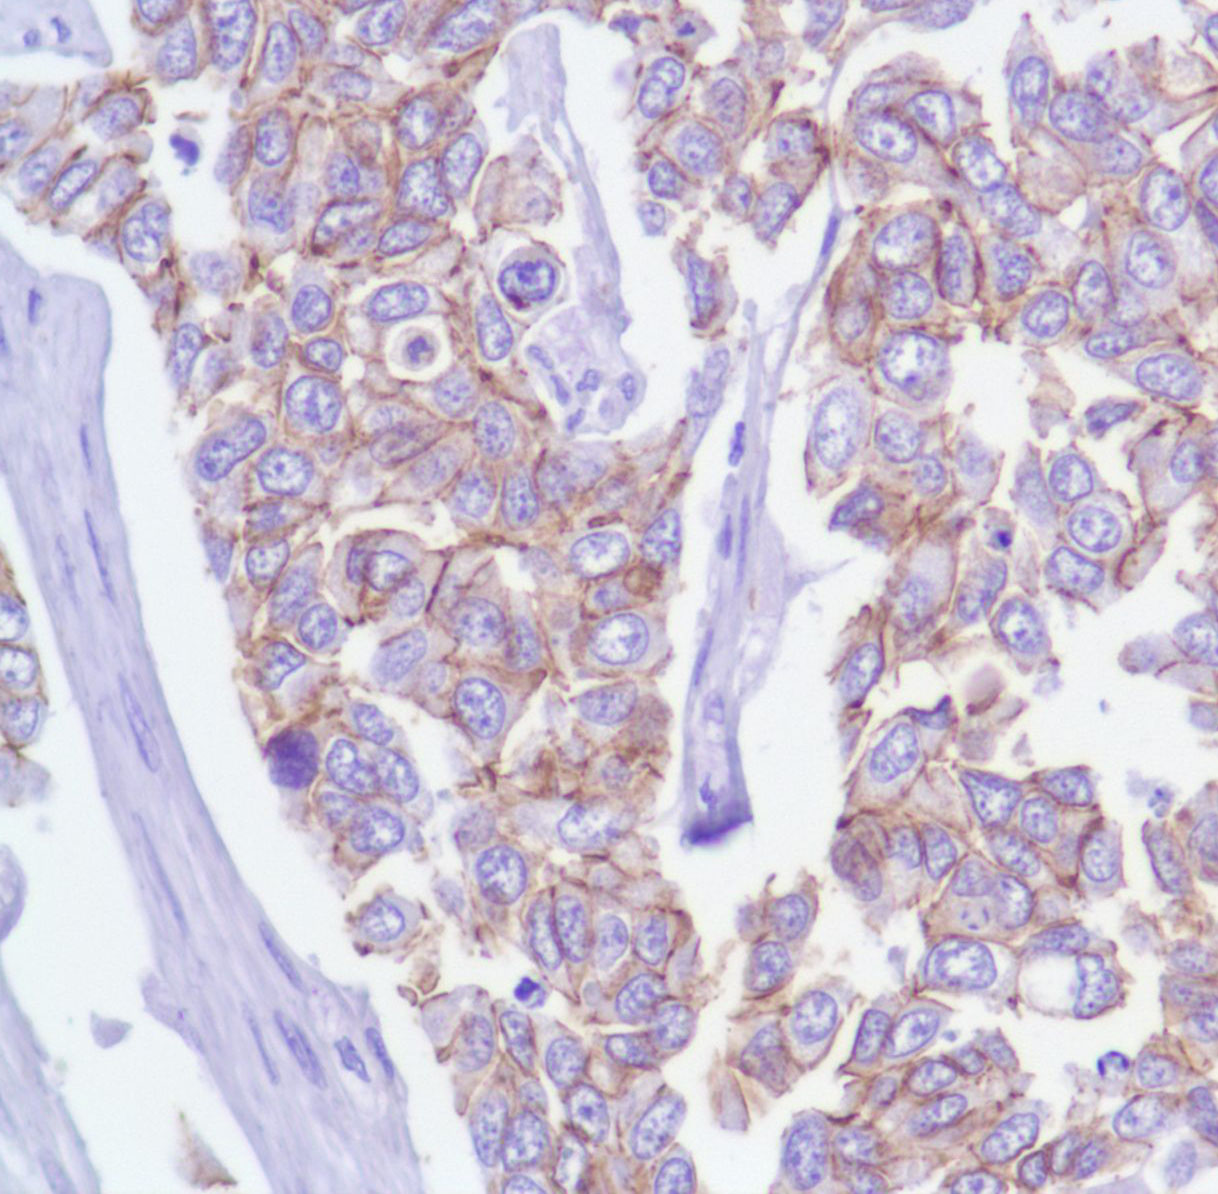

p120 (catenin delta 1) (SP63)

delta 1 Catenin (p120) is an efficient tyrosine kinase substrate implicated both in cell transformation by SRC and in ligand-induced receptor signaling through the EGF, PDGF, CSF-1 and ERBB2 receptors. The association of catenins to cadherins produces a complex which is linked to the actin filament network, and which seems to be of primary importance for cadherins cell-adhesion properties